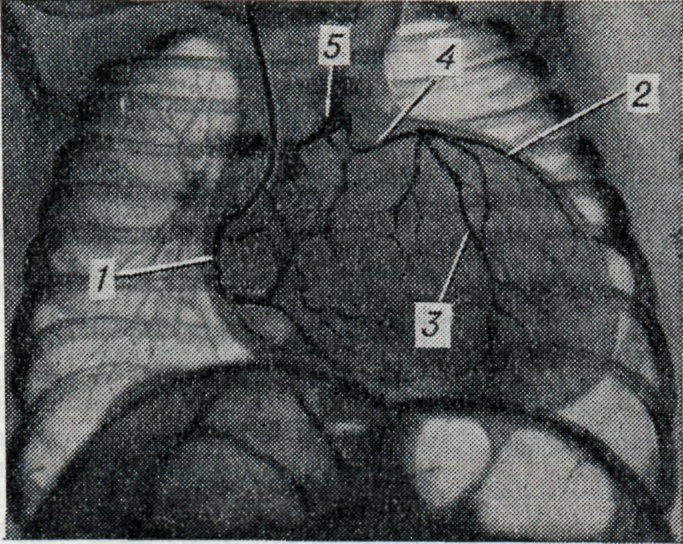

Для точного распознавания этой аномалии необходима полуселективная или селективная коронарография отходящего от аорты сосуда. При коронарографии (см.) обычно обнаруживается мощная коронарная артерия, после контрастирования к-рой отмечается ретроградное контрастирование вначале дистальных, а затем центральных отделов другой артерии и, наконец, при достаточном сбросе крови — легочного ствола (рис.). При отхождении основных коронарных артерий от аорты и аномальном отхождении добавочной артерии от легочного ствола (чаще конусной) феномен его ретроградного контрастирования наблюдается обычно при селективной коронарографии левой артерии.